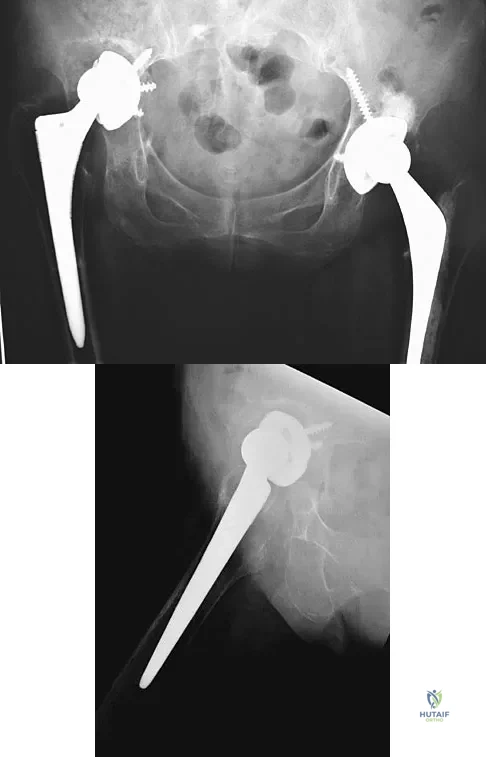

A 72-year-old woman who underwent right total hip arthroplasty 7 years ago now reports right hip pain and limb shortening. Studies for infection are negative. AP and lateral radiographs are shown in Figures 13a and 13b. What is the most appropriate management?